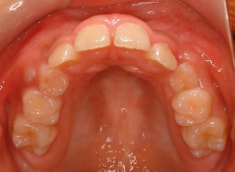

治療前

治療開始時

上顎の劣成長が顕著なので、上顎犬歯の萌出するスペースが不足しています。

また、統計通り、左上の犬歯です。